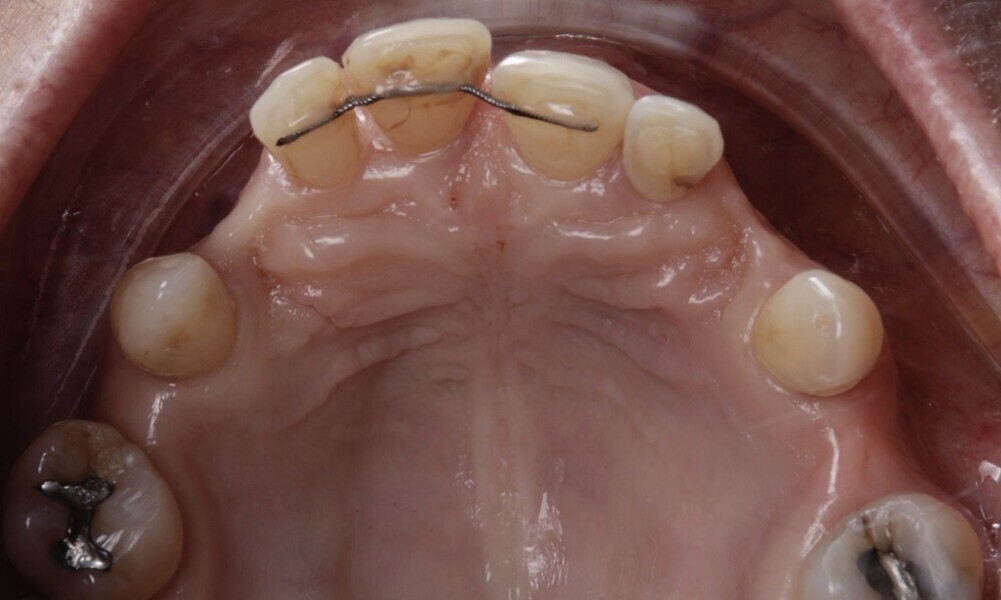

The patient wore a removable restoration in the maxillary arch and presented with anterior retainers in both the maxillary and mandibular arches owing to tooth mobility caused by periodontal disease. Teeth #15, 13, 23, 25, 27, 36, 35, 44, 45, 46 and 47 were missing. Additionally, the patient presented with several dental fillings (Figs. 4–7).

Figs. 4–7: The intra-oral examination showed generalised periodontitis, a removable maxillary restoration and multiple missing mandibular and maxillary teeth.